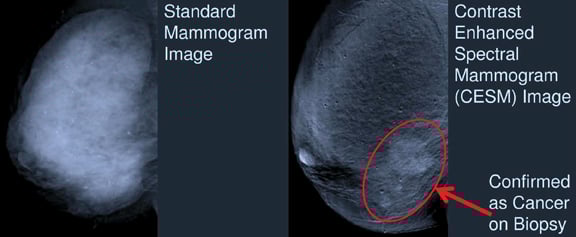

Several other emerging technologies were also highlighted at the RSNA 2013 meeting. John M. Lewin, M.D., a radiologist in Denver, discussed the use of contrast in some of these imaging trends during a breast series session. Forms of contrast-enhanced imaging include contrast-enhanced digital mammography (CEDM), contrast-enhanced spectral digital mammography (CESM), contrast-enhanced breast magnetic resonance imaging (MRI) and contrast-enhanced breast tomosynthesis (CEBT).

Maha Helal, M.D., professor of radiology at Ain Shams University in Cairo, Egypt, presented information on the use of CESM in comparison to contrast-enhanced breast MRI. CESM provides comparable information to MRI in detecting ductal carcinoma in situ (DCIS), said Helal, and is approximately one-tenth the cost and is shorter in duration. And while MRI is the most sensitive imaging test for cancer detection, according to Helal, it lacks specificity.

In her study, Helal and her colleagues compared the performance of CESM with MRI and found the newer CESM modality to be non-inferior in areas of detection and characterization of breast malignancy. These results may help to push CESM in coming years due to the modality’s applicability and cost-effectiveness.

The first technology approved for CESM in the United States is GE Healthcare’s SenoBright, which received 510(k) approval from the U.S. Food and Drug Administration (FDA) in October 2011.2 SenoBright uses X-rays at different energies to create separate but near-simultaneous exposures after contrast is injected; the resulting images highlight areas of the iodinated contrast to help localize lesions for reviewers. It is available as an upgrade on Senographe Essential, SenoCare and Senographe DS systems for GE customers.